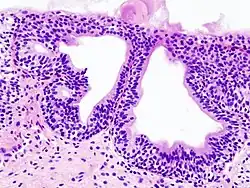

Cystitis glandularis

Cystitis glandularis at trigone

Cystitis glandularis is the transformation of mucosal cells lining the urinary bladder. They undergo glandular metaplasia, a process in which irritated tissues take on a different form, in this case that of a gland.[1] The main importance is in the findings of test results, in this case histopathology. They must distinguish a benign metaplastic change from the cancerous condition urothelial cell carcinoma.[2] It is a very common finding in bladder biopsies and cystectomies, and most often found in the trigone area. Cystitis glandularis lesions are usually present as small microscopic foci; however, occasionally it can form raised intramucosal or polypoid lesions. The cystitis glandularis lesions are within the submucosa.

Cystitis glandularis arises from and merges with Von Brunn's nests, which are groups of urothelial cells (cells of urinary tract) within the lamina propria and submucosa, formed from budding from the surface mucosa. They are considered normal. Cystitis cystica is a similar lesion to cystitis glandularis, where the central area of the Von Brunn's nests have degenerated, leaving cystic lesions. Other metaplastic entities in the urinary bladder include squamous metaplasia and nephrogenic adenoma.